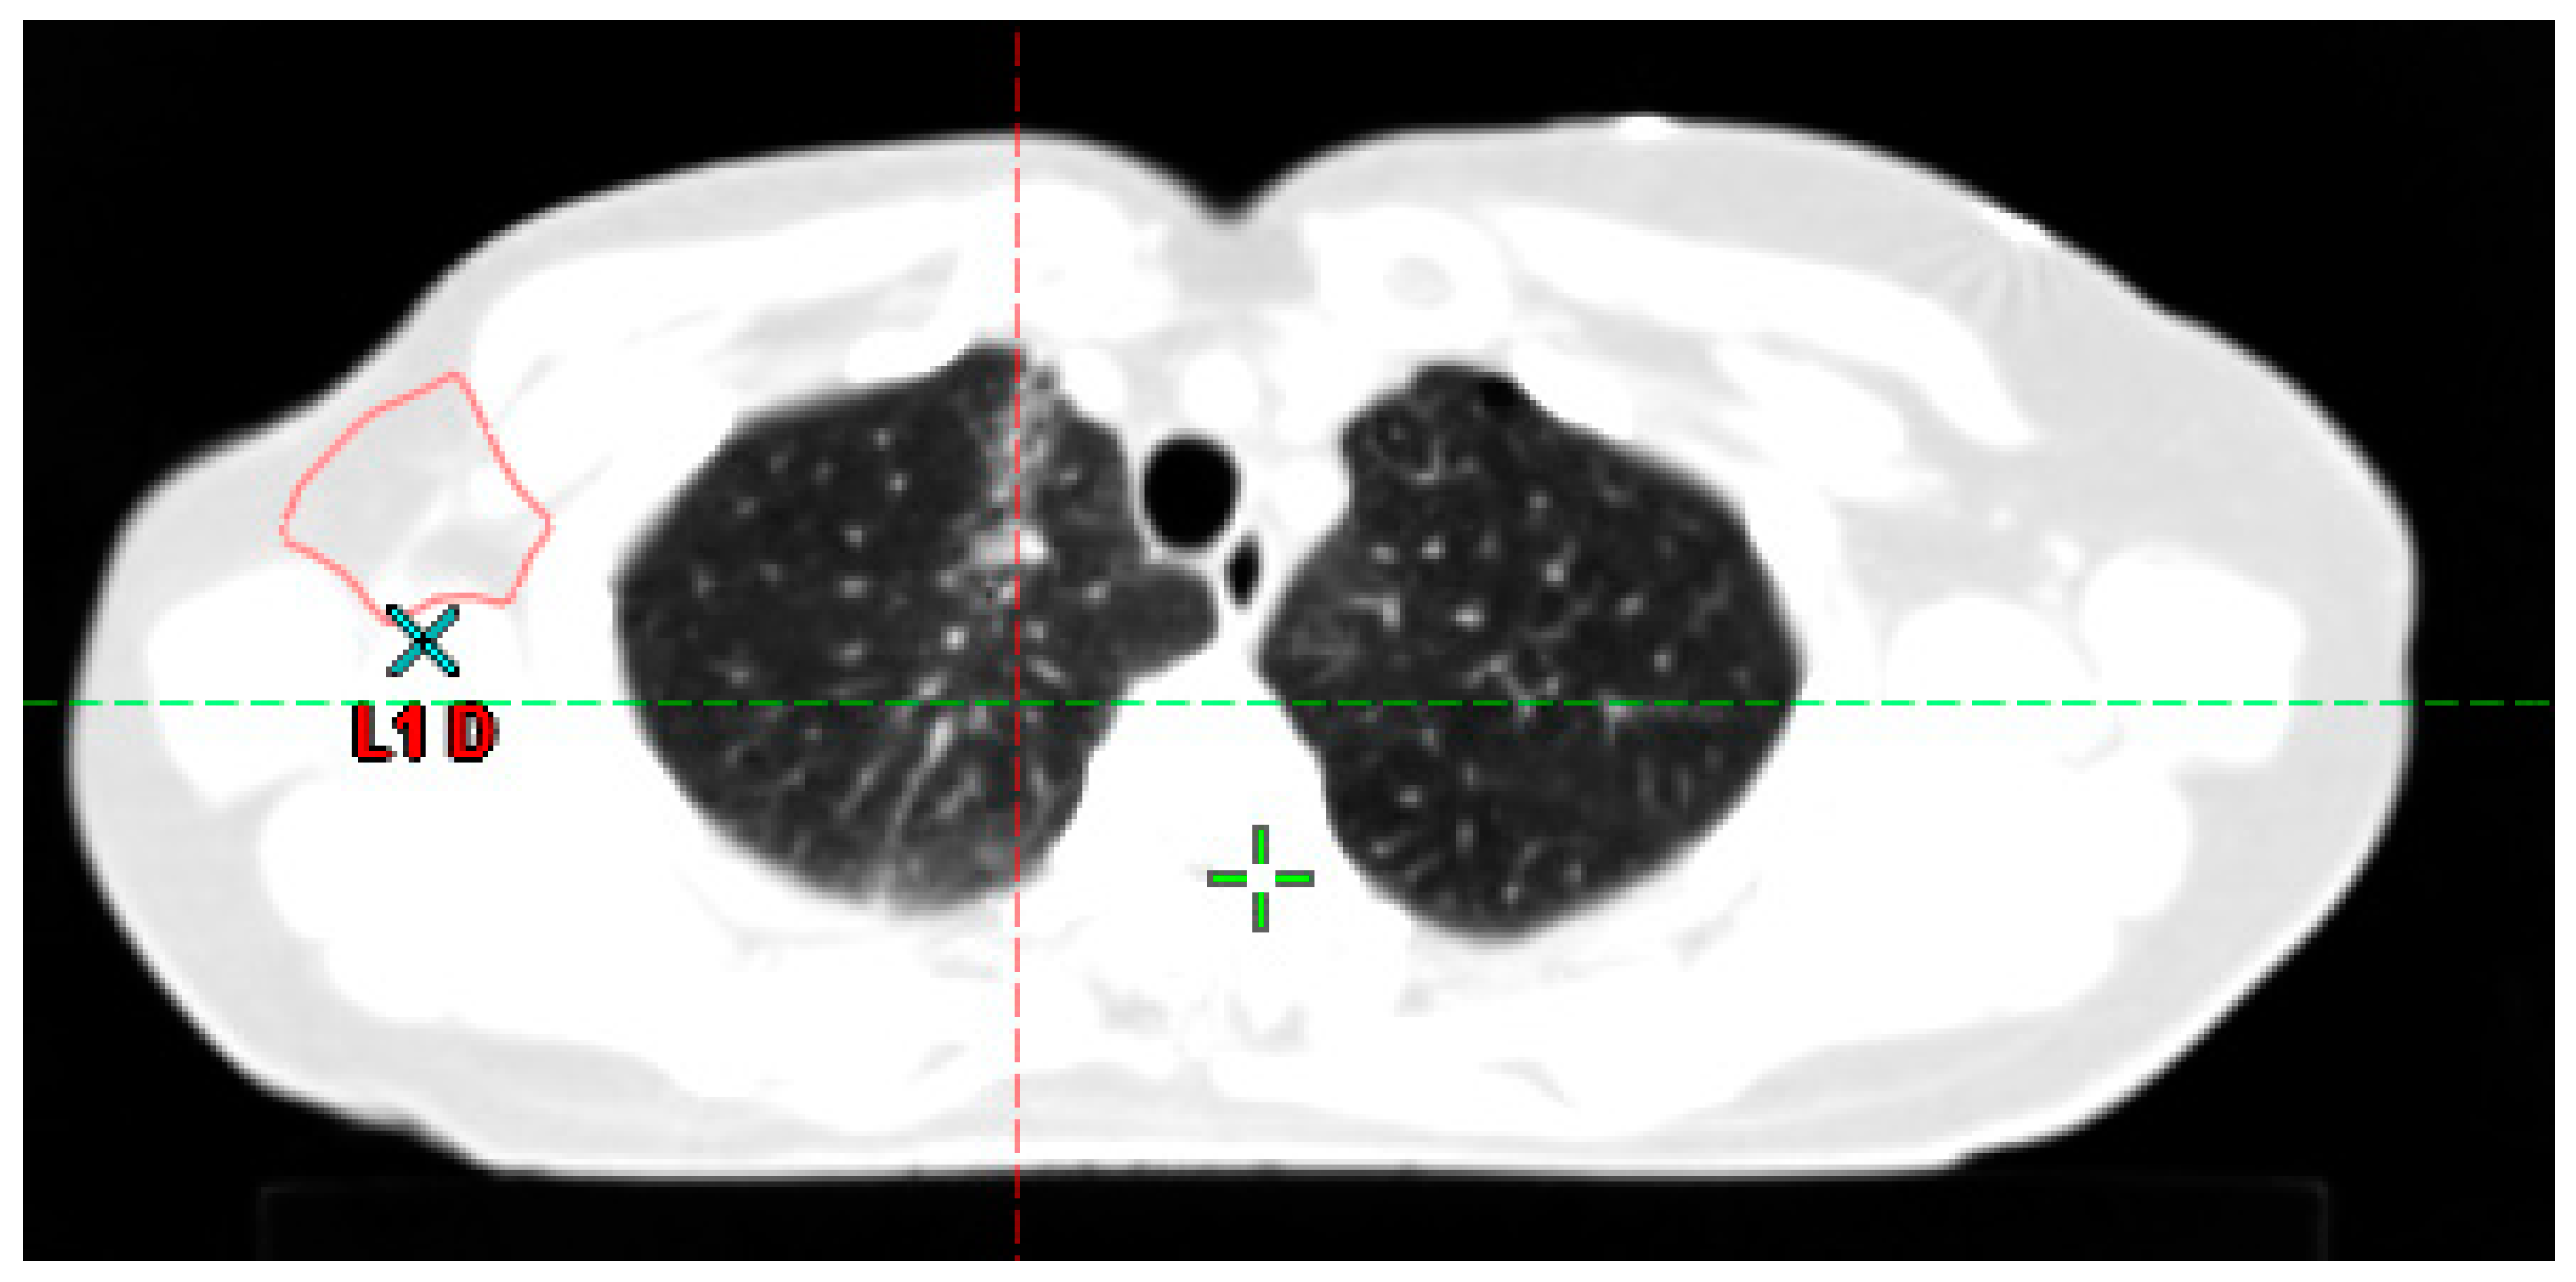

The second step, based on the simulation CT, is the definition of target volumes and organs at risk (Figure 2). This is a crucial step because the entire treatment will be based on the target volume as defined at this stage, which remains the greatest source of uncertainty in RT [45].

Beyond the GTV, there is often microscopic tumor spread, too small to be seen (even microscopically), but which can be the cause of treatment failure if not addressed. This may be direct dissemination around the tumor or into the draining vessels and lymph nodes. This volume likely to contain microscopic tumor deposits is called the clinical target volume (CTV, Figure 2A) [52]. In the context of a non-resected tumor, the construction of the CTV involves adding a margin around the GTV. This margin is determined based on anatomical considerations, incorporating knowledge of the tumor’s history, and is limited to the boundaries of healthy tissue. In certain tumor locations, such as HNC, a distinction is made between high-risk (HR) and low-risk (LR) CTV. These terms are often used in a clinical context to differentiate between various risk levels within the CTV, but they are not part of the standardized nomenclature suggested by American Association of Physicists in Medicine (AAPM) Report No. 263. The HR-CTV is constructed around the GTV, focusing on the area with the highest risk of recurrence. This region is delineated with precision to ensure that it covers the potential areas of residual disease. The LR-CTV is subsequently constructed around the HR-CTV, encompassing an area with a relatively lower risk of recurrence. This additional volume provides an additional safety margin to account for potential microscopic disease extension beyond the high-risk region. By employing this hierarchical approach in delineating the CTV, the RO aim to effectively target the areas at highest risk while still providing adequate coverage of the surrounding tissues. This approach allows for a more tailored and personalized treatment strategy for patients with non-resected tumors. Emerging deep learning approaches show promise in automating the segmentation of the CTV, aiding ROs in the future. These advanced techniques leverage artificial intelligence and neural networks to accurately delineate the CTV [53,54]. Integration of these tools into clinical practice has the potential to streamline workflow and improve consistency in CTV delineation. In postoperative RT, the GTV was resected by the surgeon. The GTV no longer exists and should therefore (and logically) not be delineated. The CTV is therefore defined as a margin around the tumor bed. In this context, registration between the simulation CT and a pretreatment PET scan may be useful to ensure that the entire initially invaded area is included in the CTV (Figure 2B,C). Numerous guidelines have been developed over the past two decades to assist radiation oncologists in defining the GTV and CTV, aiming to mitigate the risk of previously mentioned uncertainties.

Figure 2. Definition of target volumes and organ at risk. (A) The upper part of this figure depicts the process of creating the clinical target volume (CTV) as an anatomical expansion of the gross tumor volume (GTV), and the planning target volume (PTV) as an automatic expansion around the CTV. The lower part of the figure provides the axial (B) and coronal (C) views of image fusion between the simulation CT and a pre-treatment PET scan for a patient undergoing treatment for breast cancer invading the axillary (purple line), subclavicular (orange and blue lines) and supraclavicular (green line) lymph node regions. The figure emphasizes that the CTV, delineated post-neoadjuvant chemotherapy, and surgery need to encompass all the disease initially visible on the PET scan.